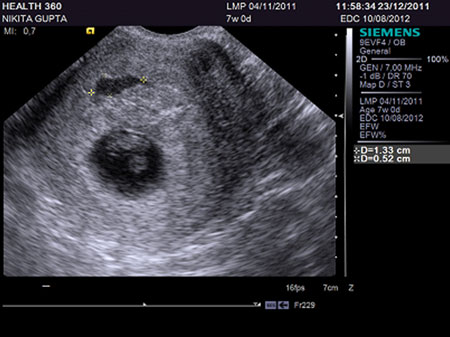

Odds Of Miscarriage After Seeing Heartbeat On Ultrasound

Ectopic Pregnancy The Role Of Ultrasonography In The ED

Use Of Ultrasound In The Provision Of Abortion - ARHP